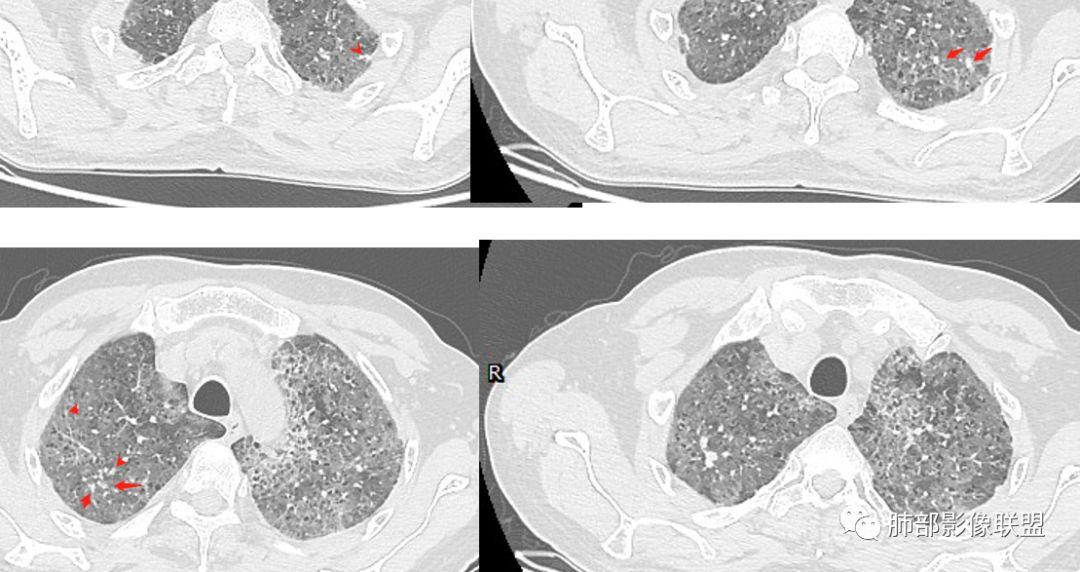

徐婕:双肺弥漫磨玻璃,铺路石,部分斑片实变。病程一年,血白细胞增高,考虑肺泡蛋白,合并双肺感染?鉴别腺癌

八爪:弥漫分布磨玻璃密度影,小叶间隔增厚,典型铺路石征,考虑PAP伴发感染性病变,鉴别特发性间质性肺炎,弥漫性腺癌,建议支气管灌洗;左肺上叶舌段不规则团片状阴影,显示不清,密切随访

笨丫头:双肺弥漫磨玻璃影,间质性改变,既往有煤炭工作史,考虑尘肺,左肺占位,边界不清,不除外合并肿瘤,腺癌?

小谢:慢性病程,无发热,双肺弥漫性病变,GGO,铺路石征,首先考虑PAP,鉴别肺腺癌

一米阳光:中老年男性,病程长。双肺弥漫性ggo,小叶间隔明显增厚,铺路石样改变,考虑PAP,鉴别pcp。建议支气管镜检查并灌洗。病史有尘肺接触史,排除尘肺合并结核

郑氏刀刀:双肺弥漫性磨玻璃影,伴铺路石征,下叶为主,且见斑片实变影,白细胞高,结合执业史,尘肺,PAP伴感染,腺癌待排。

小景:双肺弥漫磨玻璃影,小叶间隔增厚,呈碎石路征。患者粉尘接触史,考虑PAP。左肺舌段病灶,抗感染无吸收,腺癌待排。

小赵:中老年男性患者。慢性病程,多次咳黄痰,治疗效果一般,反复发生。CT表现为双肺弥漫磨玻璃样改变,并呈细网格样铺路石状改变,上下肺无明显差异。双下肺为主多发渗出实变,边界不清,抗炎治疗后病变吸收不明显,局部似有进展。考虑肺泡蛋白沉积症基础上合并感染。肿瘤标志物高,中老年患者,肺炎型肺癌不除外。

上肺为主小叶中心型肺气肿——吸烟

碎石路征,下肺为主

肺部结节

左上叶斑片状高密度影

1、GGO+网格——碎石路征

2、分布无特定位置,较随机

3、可有少许实变——部分与层厚有关

4、小叶间隔内静脉增粗

5、病灶较多时部分可见重力趋势

1.由于脂蛋白的沉积和占据,肺泡腔含气量减少,这是影像上较大范围“磨玻璃影”的基础。

2.由液体、细胞浸润和纤维组织造成的小叶间隔增厚是影像上多边形“铺路石征”的基础。

3.显眼的小叶间隔对病灶有阻挡作用是形成影像上“地图样改变”的基础。我们观察到的病灶与临近相对正常肺组织之间常常有比较清楚的分界。